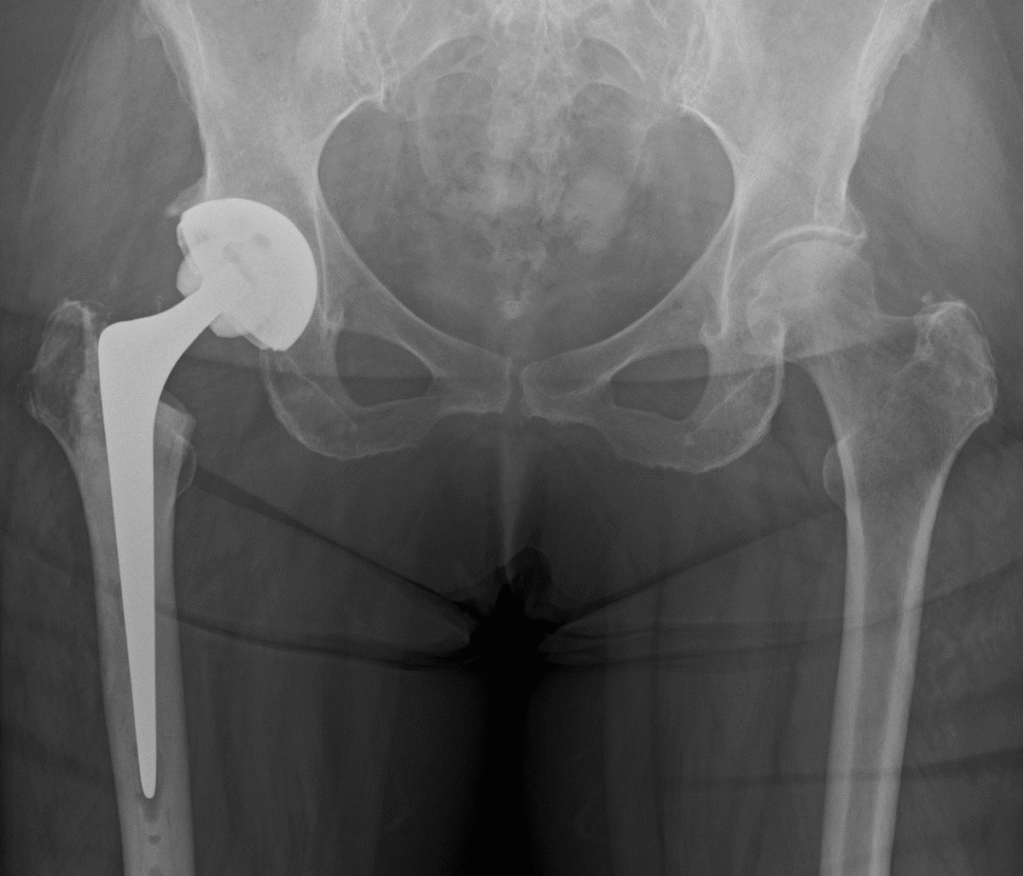

Hip arthritis is the wear-and-tear or inflammation of the hip joint that leads to pain, stiffness and reduced mobility. The hip is a ball-and-socket joint formed by the head of the femur (thigh bone) and the acetabulum (socket) of the pelvis. When the cartilage that cushions the joint wears away, bones rub together, causing pain and limiting everyday activities.

- X‑rays: The primary test to assess joint space, bone spurs and deformity.

- Advanced imaging: MRI or CT scans used selectively (for suspected avascular necrosis, unexplained pain, or pre‑surgical planning).

Mr. Radja offers modern techniques including muscle‑sparing approaches and robotic-assisted implantation where appropriate, which may improve precision and early recovery.

What to expect after hip replacement

- Day 0–1: Mobilise with physiotherapy; most patients start walking with aids.

- Weeks 1–6: Pain falls rapidly; continue physiotherapy to rebuild strength and gait.

- 6–12 weeks: Many return to light work and low‑impact activities.

- 3–6 months: Significant functional improvement and most daily activities achievable.

- 12 months: Full recovery and maximal improvement for most patients.